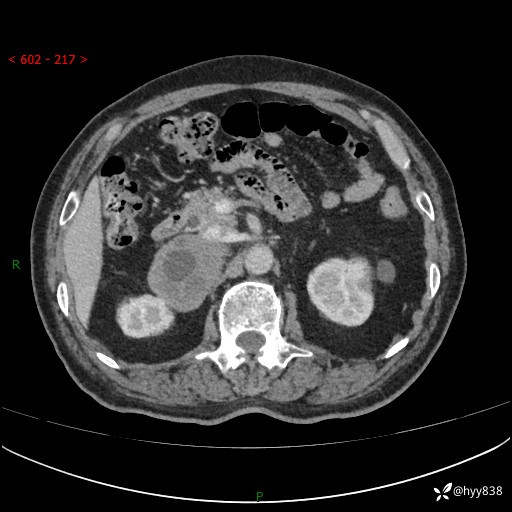

【患者信息】:76岁/男

【主诉】:检查发现右侧肾上腺占位6天

【现病史及既往史】:患者6天前体检发现右侧肾上腺占位,无腰痛,无放射痛,无尿频、尿急、尿痛及肉眼血尿,无畏寒、发热,无恶心、呕吐,今为求进一步治疗,遂来我院就诊,门诊拟“右侧肾上腺占位”收住入院。 起病以来,患者精神、饮食、睡眠可,大小便如常,体力体重无明显变化。

【检查】:肾上腺CT平扫+增强